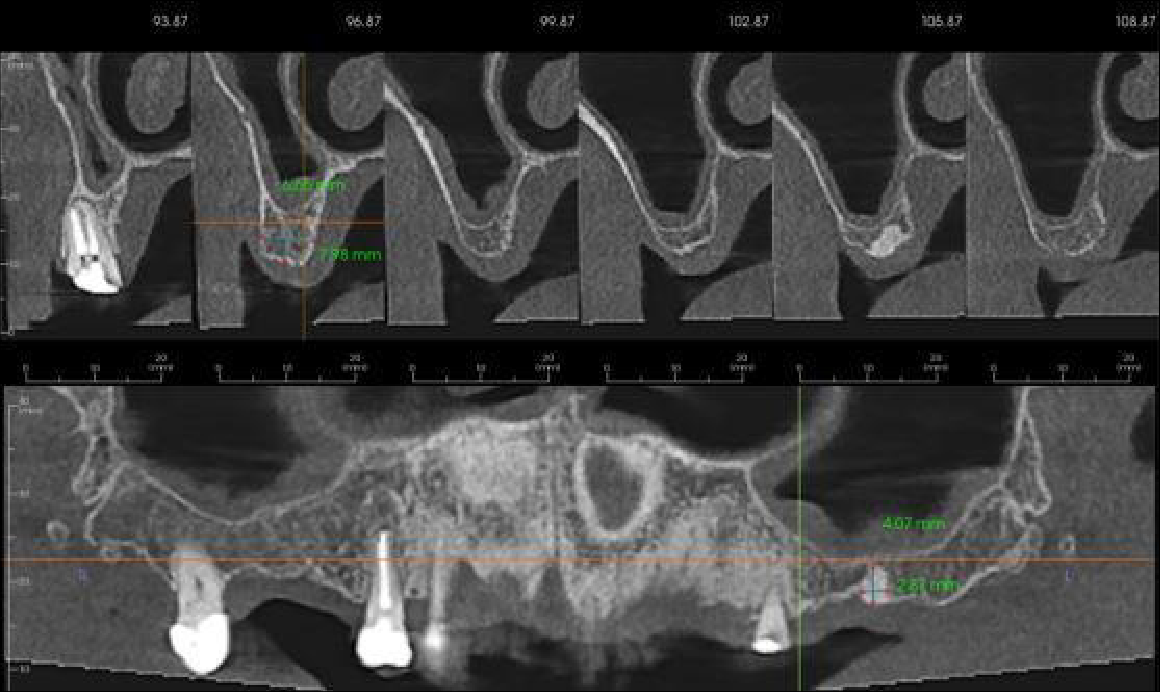

Reconstructed panoramic view of the maxilla

UR7-4 region cross sections at 2 mm intervals. Moderate loss in vertical bone height. The UR4 is root treated. The buccal root filling is short of the apex with 3-4 mm wide apical radiolucency. The palatal root canal is filled to the apex with 0.5-1 mm wide radiolucency

UL3-4 region cross sections at 3 mm intervals. Mild loss in vertical bone height. Moderate density cortical and trabeculae bone

UL5-7 region cross sections at 3 mm intervals. Moderate loss in vertical bone height. Moderate density cortical and trabeculae bone